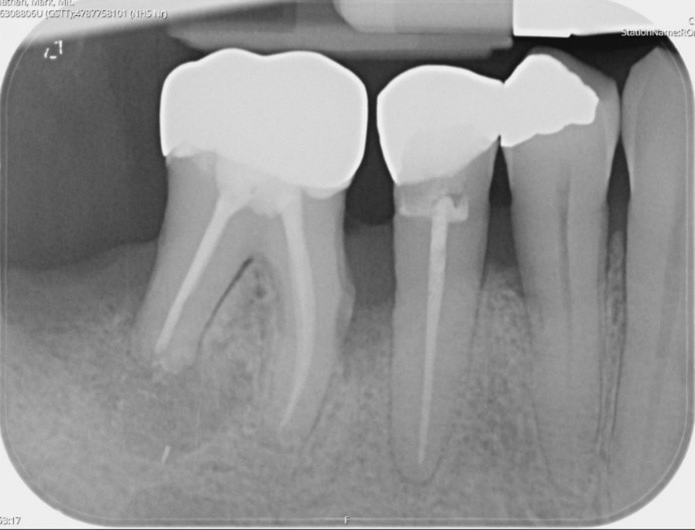

LR6: Root canal retreatment & internal root resorption management and cuspal coverage

UL6 Internal inflammatory resorption perforating palatal root. Repaired with MTA.

12 month review (crown carried out by GDP)

Molar endodontics

Pre-operative

Post-operative